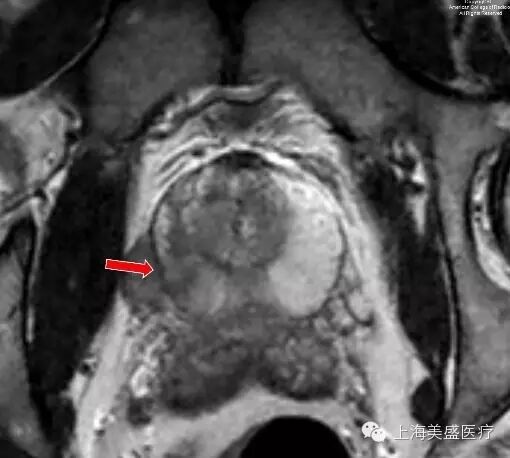

图 1. 横断 T2 示前列腺外周带右侧区异常低信号(箭头示)